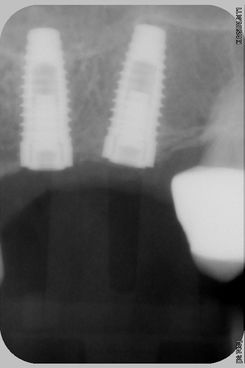

003.TIF

..si noti la Rx eseguita subito dopo l'inserimento dei due impianti..